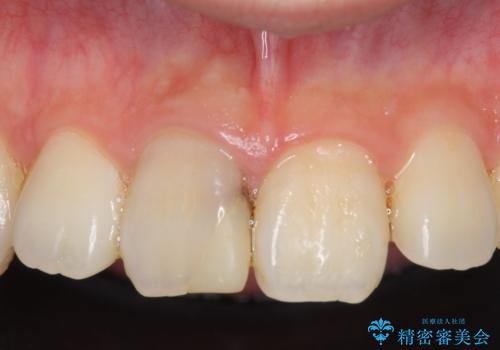

- 右上1番目の前歯の変色が気になるといらっしゃった方の症例です。

再根管治療後、オールセラミッククラウンによる補綴を行いました。

今回用いたオールセラミッククラウンはジルコニアフレームという白い素材の上にセラミックを盛っているため、審美性が非常に高いのが特徴です。